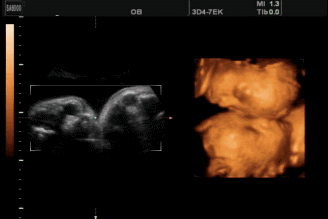

李想丽,女,超声诊断医师,具有执业医师和CDFI医师资格,在某地方医院从事超声工作10余年。曾在兰州大学第一附属医院超声科进修学习。擅长四维超声胎儿畸形筛查、腹部脏器、浅表脏器、妇产科彩超检查。

为了能更准确的检查胎儿是否健康,善懿堂诊所引进了我县首台高端四维彩超,不仅能检查胎儿是否健康,还能为胎儿拍宫内写真,受到了不少准爸妈的青睐。

四维彩超的检查时间有着很大的学问,只有在最佳时间里检查才能获得比较全面的检查效果,一般认为孕20周至28周是四维彩超检查的最佳时间。因为这个时段胎儿的肢体及各主要脏器已经全部发育,而且羊水较适合做胎儿畸形筛查。

1、全方位、多角度观察:四维彩超可以全方位、多角度地了解胎儿在宫内的生长发育状况,能够在早期诊断胎儿先天性身体表面畸形和先天性心脏疾病提供正确的科学依据。

3、胎儿体表检查:四维彩超还可以对胎儿的身体表面进行全面的检查,如唇裂,脊柱裂,脑积水,无脑儿,小头畸形,肾积水、心脏先天畸形、骨骼发育不健全等,提供了准确的科学的依据,并能及早的治疗。

4、实时动态活动图像:可以清楚的展示胎儿在宫内的实时动态活动图像。还可以将宝宝的样子以及动作制作成照片或动态视频,那么就可以让宝宝拥有最完整的0岁相册。